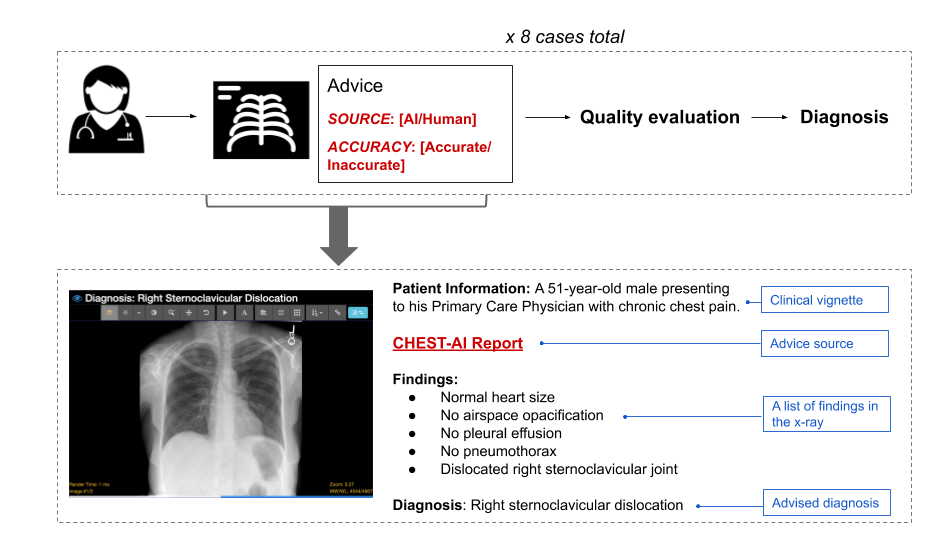

Our paper focuses on how expert and non-expert physicians modulate their trust in AI-generated advice in order to walk a tight line: if physicians do not trust AI advice they will not use it, but blind trust could lead to medical errors. To evaluate this dynamic, we presented radiologists and internal/emergency medicine (IM/EM) physicians with a series of chest x-rays and diagnostic advice. We varied two things: whether we presented the advice as coming from an AI system or a fellow radiologist, and whether the advice was correct or incorrect.